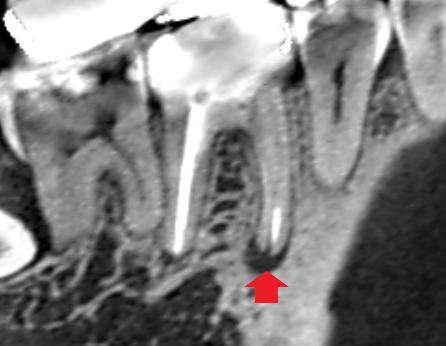

初診時の下顎第一大臼歯の近心根の冠状断のCT画像です。

根の先に膿の影がみられます。赤い矢印の先に2本の根管充填がみられます。この根管と根管の間にイスムスがあり、そこに残存している神経組織が腐敗し根管を汚染していることも考えられます。